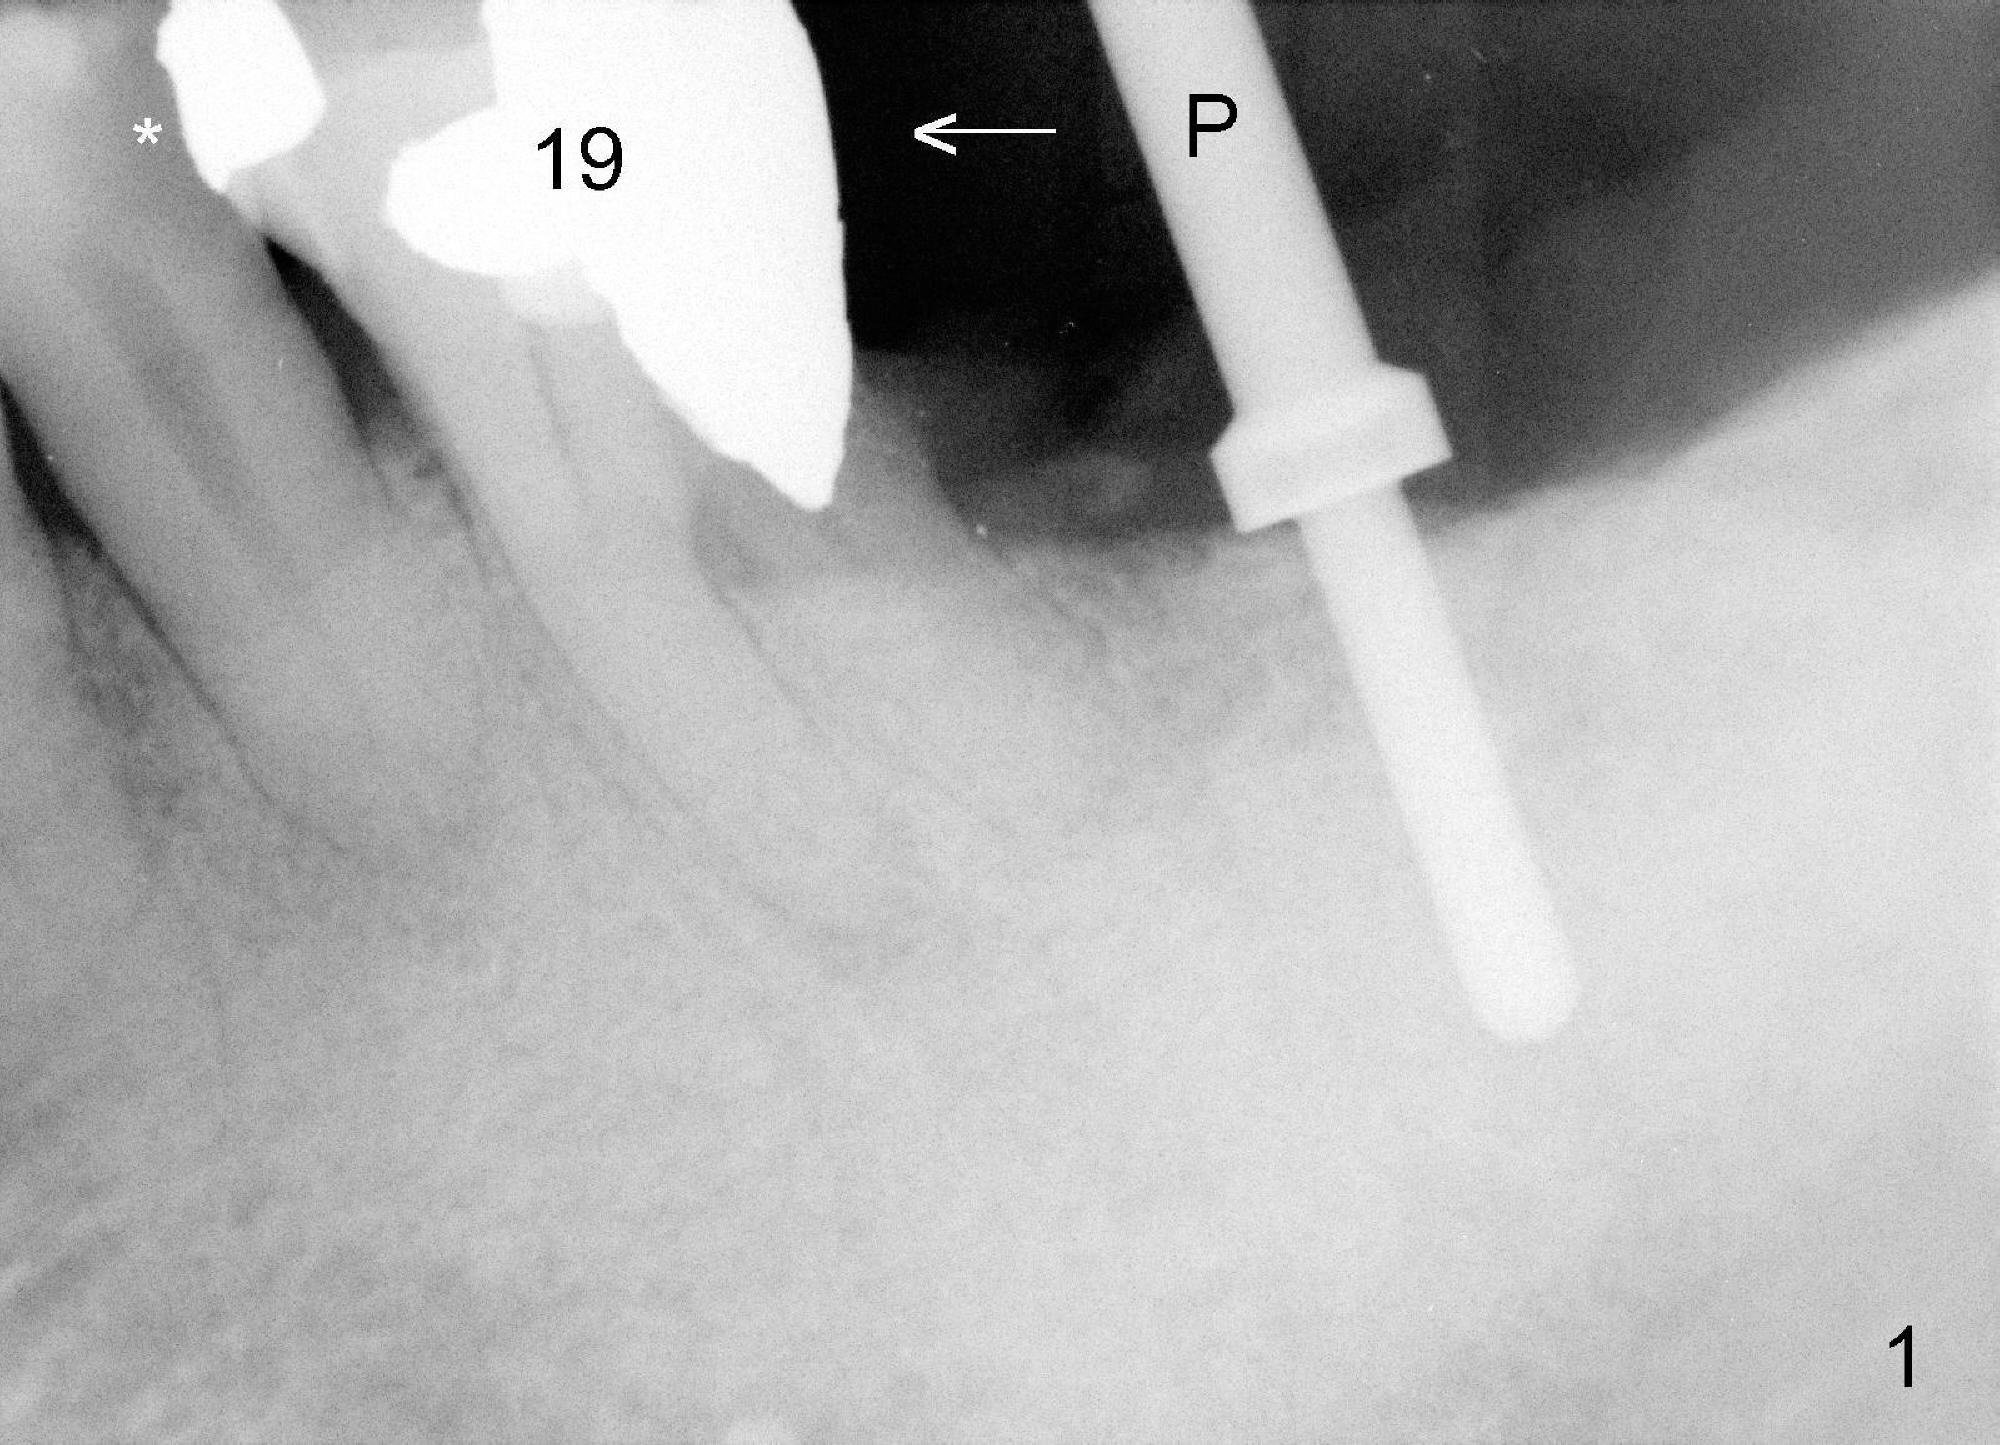

The 69-year-old male is a dental phobic with poor dentition. He wants to an implant at the site of #18 first and refuses to have the tooth #11 (with asymptomatic apical abscess) extracted. To reduce chance of post-implant infection, the implant is placed in a two stage manner. The distal amalgam overhang of the tooth #19 is removed by Piezo scaler (Fig.1). An incision is made. After a 2 mm pilot drill, a parallel pin is inserted; it appears that the coronal end of the trajectory should be leaned mesially (Fig.1 arrow). Since the ridge is wide, an extra wide implant is placed (Fig.2 I: 5.9x10 mm with insertion torque >50 Ncm) with one distal thread exposed (Fig.2,3 <). The disto-occlusal caries of the tooth #20 (Fig.1,4 *) is going to be excavated.